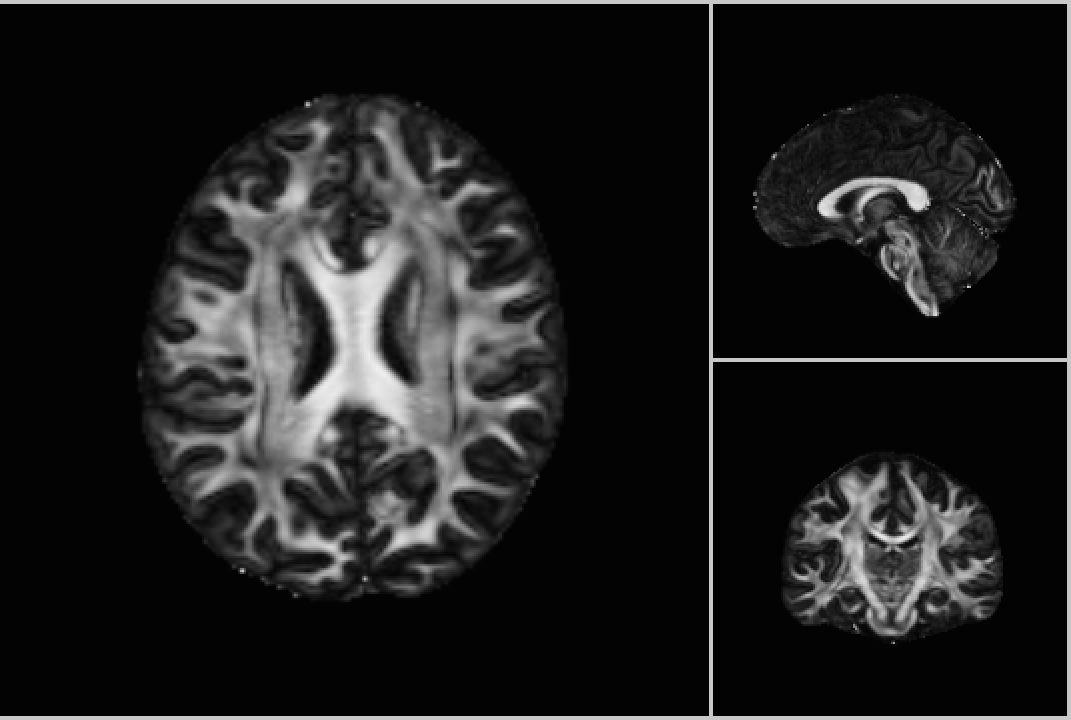

Refer to caption

Figure 2: Orthogonal slices of Mask and Fractional Anisotropy values for a single subject.

Segmentation: Step  1N constructs a 3D mask that segments each image volume into two parts: one with the part to be analyzed, i.e., the brain, and the other with uninteresting background. As the brain comprises around two-thirds of the image volume, using the generated mask to filter out the background will speed up subsequent steps. Segmentation proceeds in three sub-steps. First, we select the subset of volumes with no diffusion weighting applied. These images are used for segmentation as they have higher signal-to-noise ratio. Next, we compute a mean image from the selected volumes by averaging the value of each voxel. Finally, we apply the Otsu segmentation algorithm [27] to the mean volume to create a mask volume per subject. As an illustration, 2(a) shows the orthogonal slices of the binary mask for a single subject.

The model parameters are summarized as a scalar for each voxel called Fractional Anistropy (FA) that quantifies diffusivity differences across different direction. 2(b) shows orthogonal slices of the FA values for a single subject.